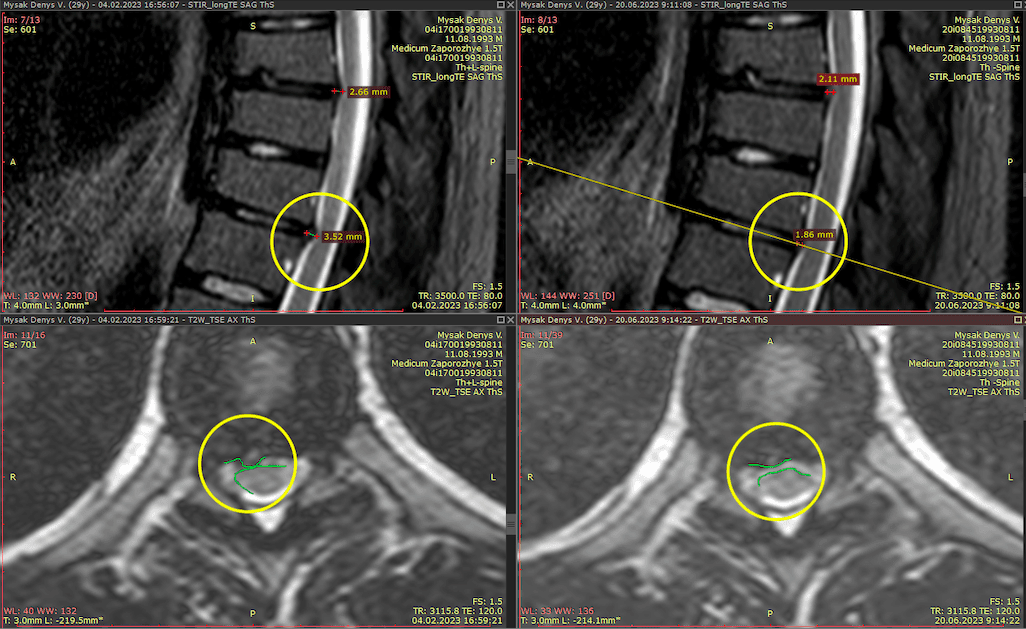

Метод лікування грижі шляхом стимуляції резорбції в Україні був впроваджений у 2020-2021 роках.  Алгоритм оцінки грижі на предмет резорбції, що використовується у клініках – є авторським, розроблений лікарем Боханом А.Ю.